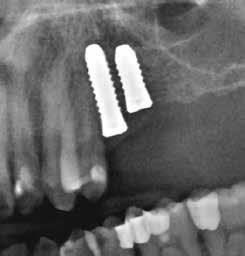

A CT metszetekben a 48-as gyökerei körbeölelik a canalis mandibularist, amelyet piros nyíllal jelöltünk a fotókon.

Szeretnék mutatni néhány ábrát az egyik bonyolult esetről, a közelmúltból. A CT-n látszik, hogy a három gyökér teljesen „körbenőtte” az ideget. Van olyan frontális metszeti kép, ahol csak a gyökerek vannak a nervus körül, ezen a szakaszon egyáltalán nincs meg a csontos fala a canalisnak. Szeparációs technikával, viszonylag könnyen, minimális traumával, szövődménymentesen sikerült eltávolítani a fog minden részét. A várakozásnak megfelelően, a beteg nem számolt be paraesthesiáról.